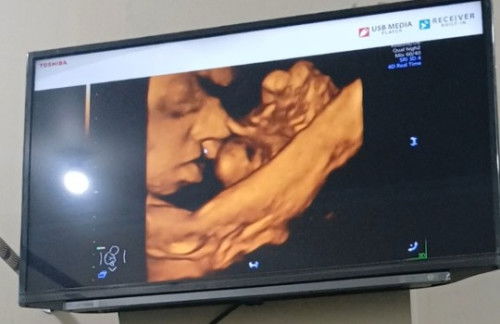

Kelainan janin

Sedih banget ya Allah usg di 32 week baru keliatan kalau ternyata anakku ada celah diantara bibir d😭 Padahal di usg sebelumnya gak terlihat ya Allah semoga ini suatu kesalahan alat😭 Apa ada yang sama bun, gimana caranya biar hati tenang